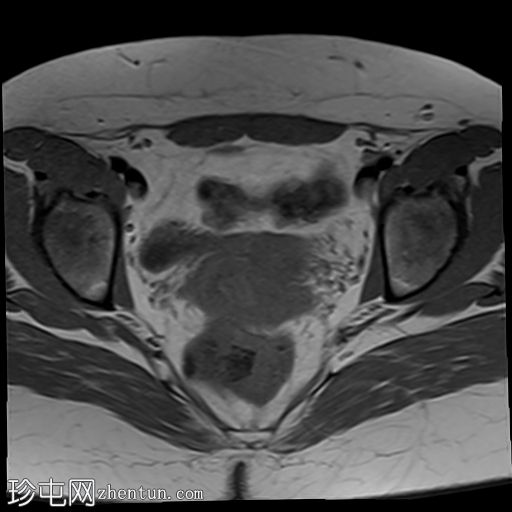

轴位

T2加权像

双侧卵巢位置接近(卵巢相吻),左侧卵巢内可见一边界清晰的囊性病变,大小约3.1 × 2.7 × 2.9 cm,T1加权像呈高信号,T2加权像可见暗点征及内部暗点征。以上MRI特征符合卵巢子宫内膜异位囊肿的诊断。

右侧卵巢可见一囊肿,大小约为 2.8 × 2.0 × 2.2 cm,T1 加权像呈高信号,囊内可见液-液平面,提示囊内含有不同时期的出血性物质。由于对侧卵巢存在典型的子宫内膜异位囊肿,且该囊肿无强化,影像学表现强烈提示为另一子宫内膜异位囊肿。

双侧卵巢均可见多个小卵泡。